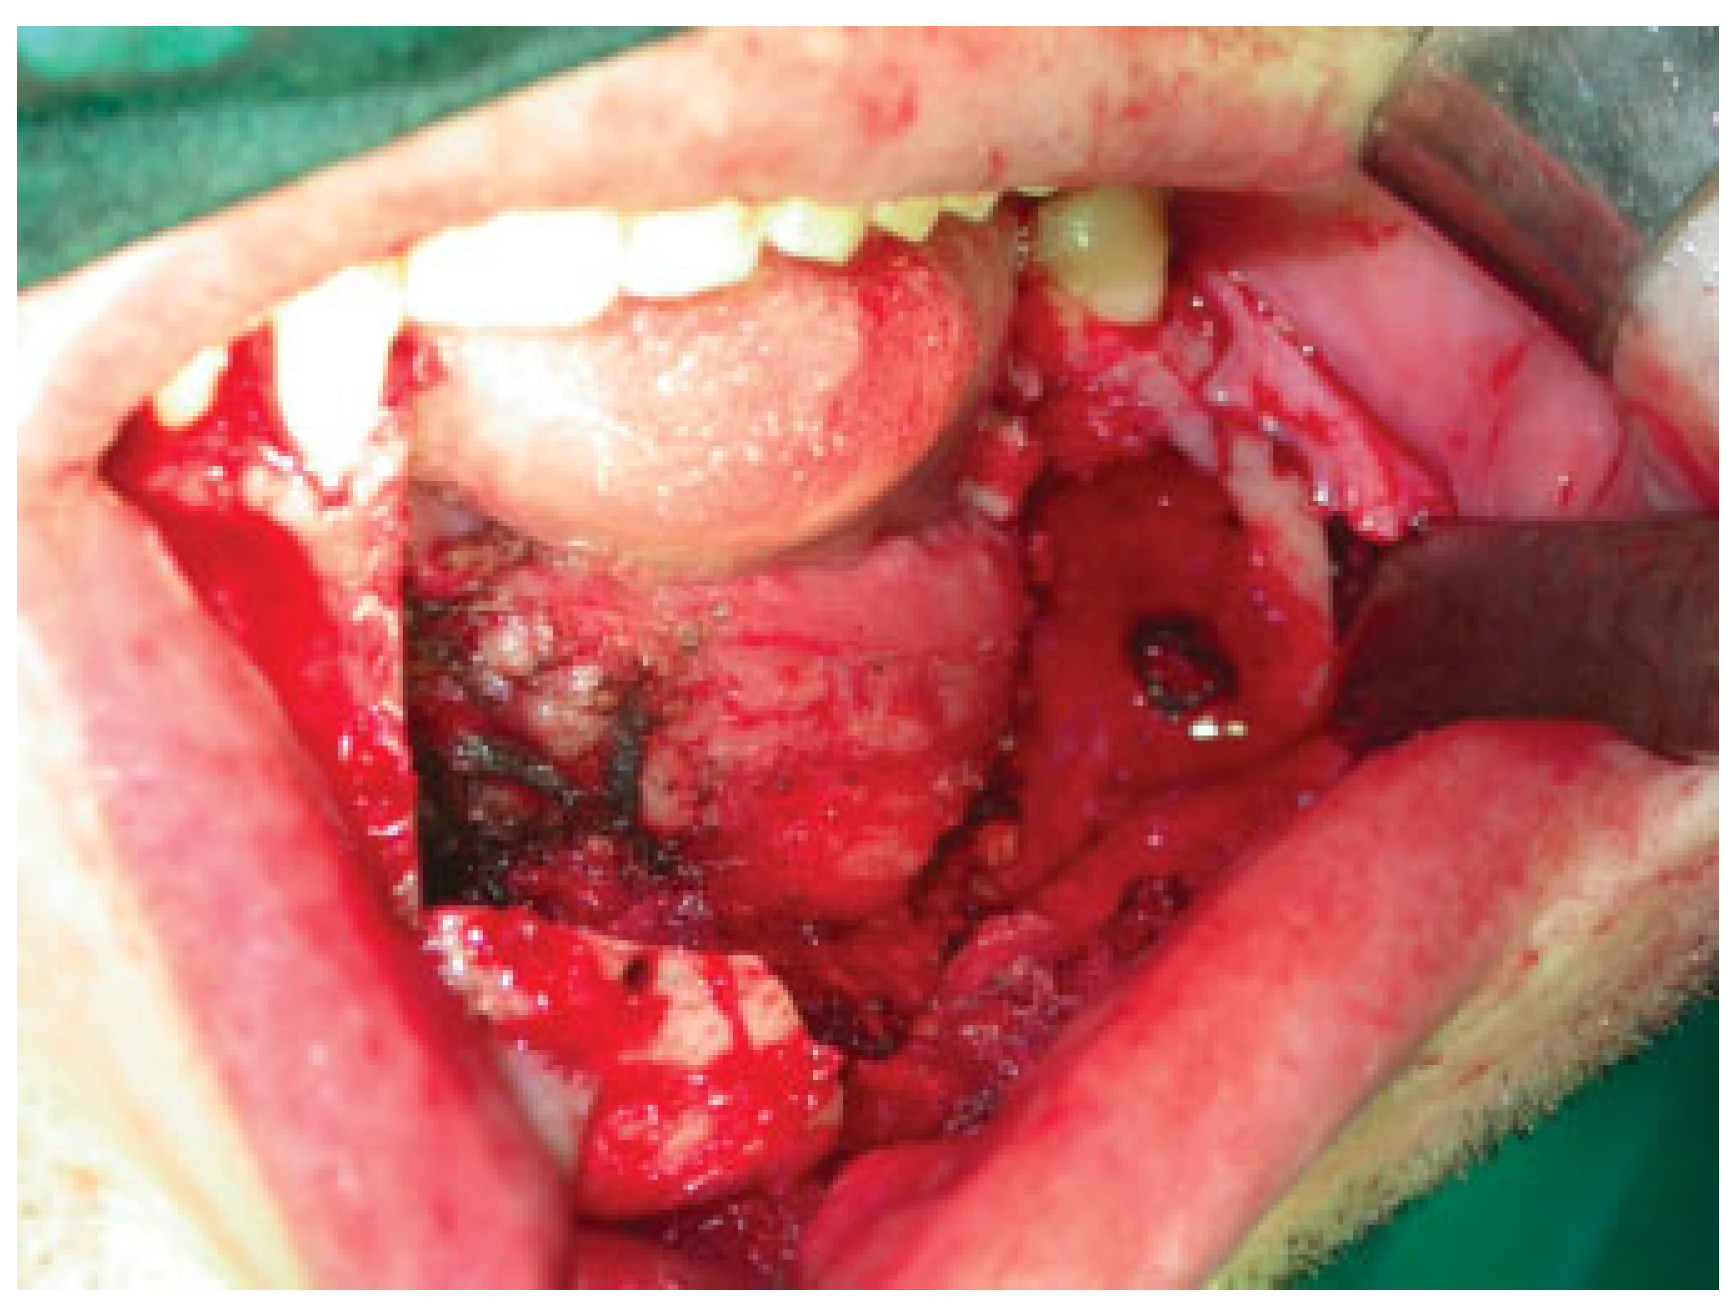

Tumor was excised via both intraoral and extraoral approaches in the submandibular region (Figure 1 and Figure 2).

Marginal mandibular branch of the facial nerve was preserved, and segmental mandibulectomy was performed from distal left canine up to left third molar.

Figure 1. Mandibular defect after osteotomy from left canine to left third molar.